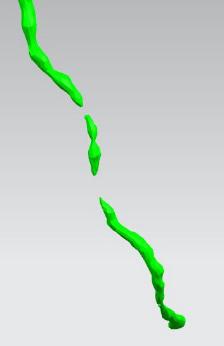

首先通过病人的心脏冠脉造影CT数据,获取病人的心脏冠脉三维模型。

病人的冠脉造影CT数据 提取出的冠脉三维数据